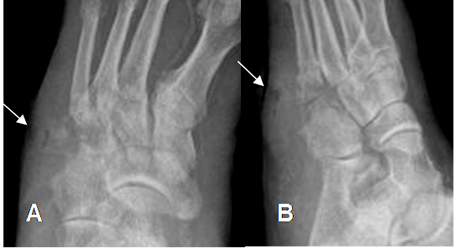

Fig 126 A. Pie diabético.

A: Rx AP y B: Rx oblicua del pie. Ausencia de las falanges del 4º y 5º dedo, por amputaciones previas. Calcificación en las paredes de los vasos, por angiopatía diabética. (Flechas).